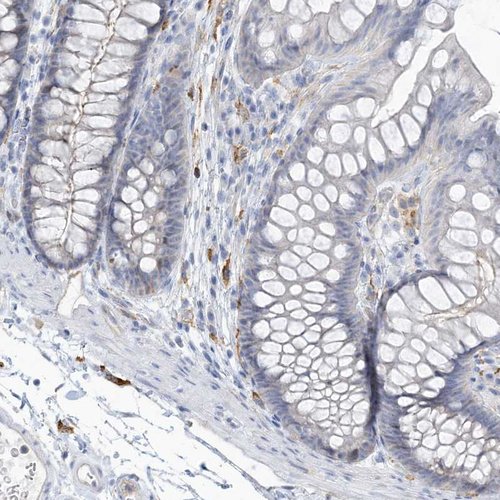

Immunohistochemical staining of human bone marrow shows moderate membranous positivity in hematopoietic cells.